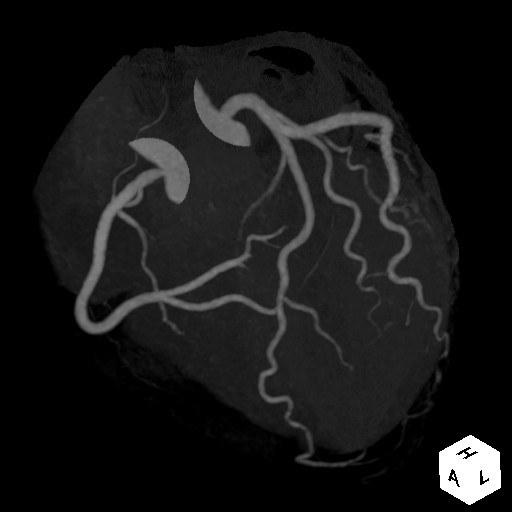

写真 MIP画像

MIP画像:心臓カテ-テル検査と同じように観察することができます。